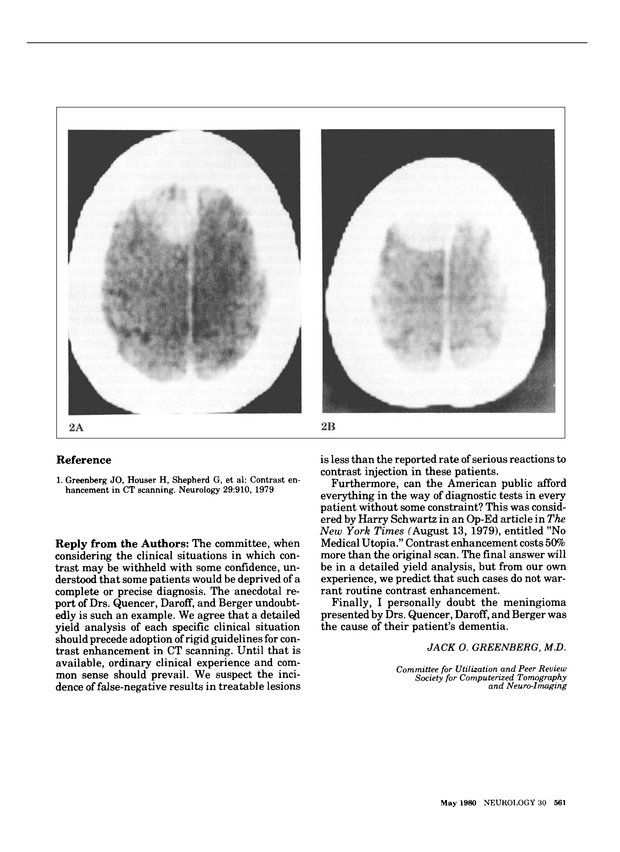

对比增强CT扫描

杰克·o·格林伯格